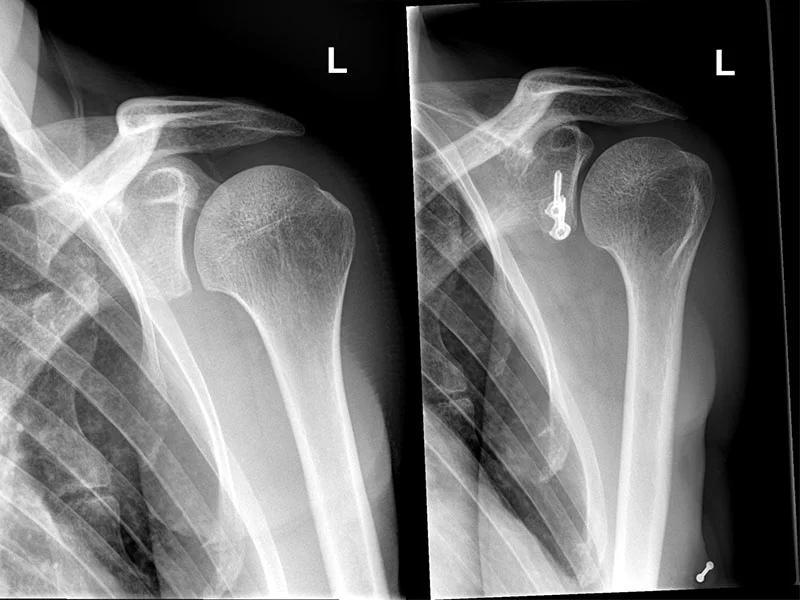

Ab zwei bis drei erfolgten Luxationen ist das Stadium einer chronische Instabilität erreicht. Mit konservativen Massnahmen kann hier keine Besserung erwartet werden. Mit Anpassung der sportlichen Tätigkeit kann das Risiko der Reluxation vermindert werden, jedoch nicht relevant verbessert werden. Deshalb bleibt die operative Therapie nur noch als letzte Option. Hier kommt vor allem ein Korakoidtransfer (Operation nach Latarjet) zum Zug. Dazu wird der Rabenschnabelfortsatz (Korakoid) an die Gelenkspfanne mit Schrauben fixiert. Die Resultate dieses Eingriffs sind sehr gut.

Bei jeder Luxation kommt es zur Verletzung der vorderen Bandstrukturen (sogenannte Bankart-Läsion) wie auch einer Impressionsfraktur am Oberarm (sogenannte Hill-Sachs Läsion). Weiterhin kann es auch zu einer Fraktur der Gelenkspfanne kommen.

Ist die Hill-Sachs-Läsion klein und eine isolierte Verletzung der Bänder vorhanden, kann eine arthroskopische Refixation der Bänder in Erwägung gezogen werden. Ist jedoch ein Defekt der Pfanne vorhanden, kommt der Korakoidtransfer zum Zug.